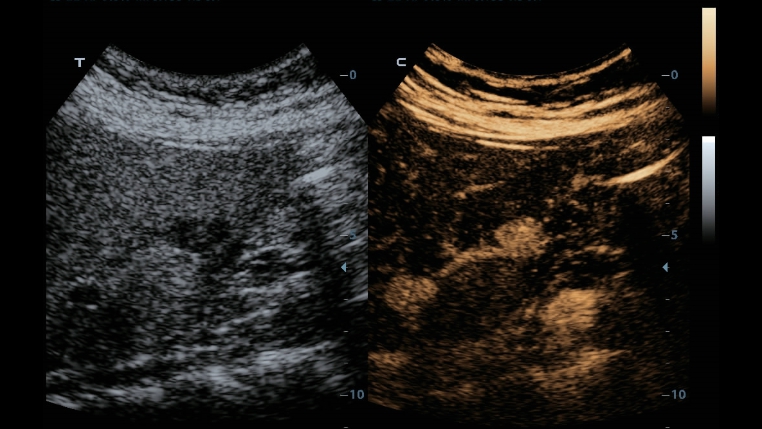

Klassieke beeldvormingstechnologie?n: verbetering van de kwaliteit voor diagnoses

DC-40 met Full HD maakt gebruik van klassieke beeldvormingstechnologie?n die van gevestigde ultrasoundsystemen zijn gemigreerd om u beelddetails van betere kwaliteit te bieden.

- iClear (beeldvormingstechnologie die spikkels reduceert)

- PSH (Phase Shift Harmonic-beeldvorming)

- iBeam: ruimtelijke beeldvormingstechnologie